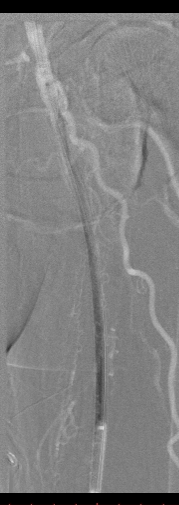

病例-1 男性,77岁,左下肢SFA支架术后7年,旁路术后3年静息痛 ABI:左侧 0.35